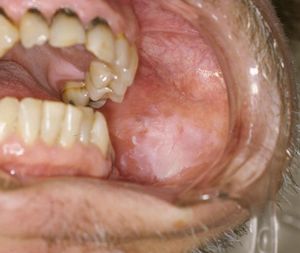

The white lesion هي مثال للطلوان.

الطَلَوان ( Leukoplakia ) عبارة عن بقع بيضاء تظهر في الغشاء المُخاطِيُّ للفم. ويكون الرجال هم أكثر عرضة للاصابة بهذا المرض أكثر من النساء بما يقارب الثلاثة اضعاف. والعمر الذي يظهر فيه الاصابة به عادة هو ما بعد الاربعين، مع احتمالية الاصابة به في اعمار اصغر من ذلك أيضا.